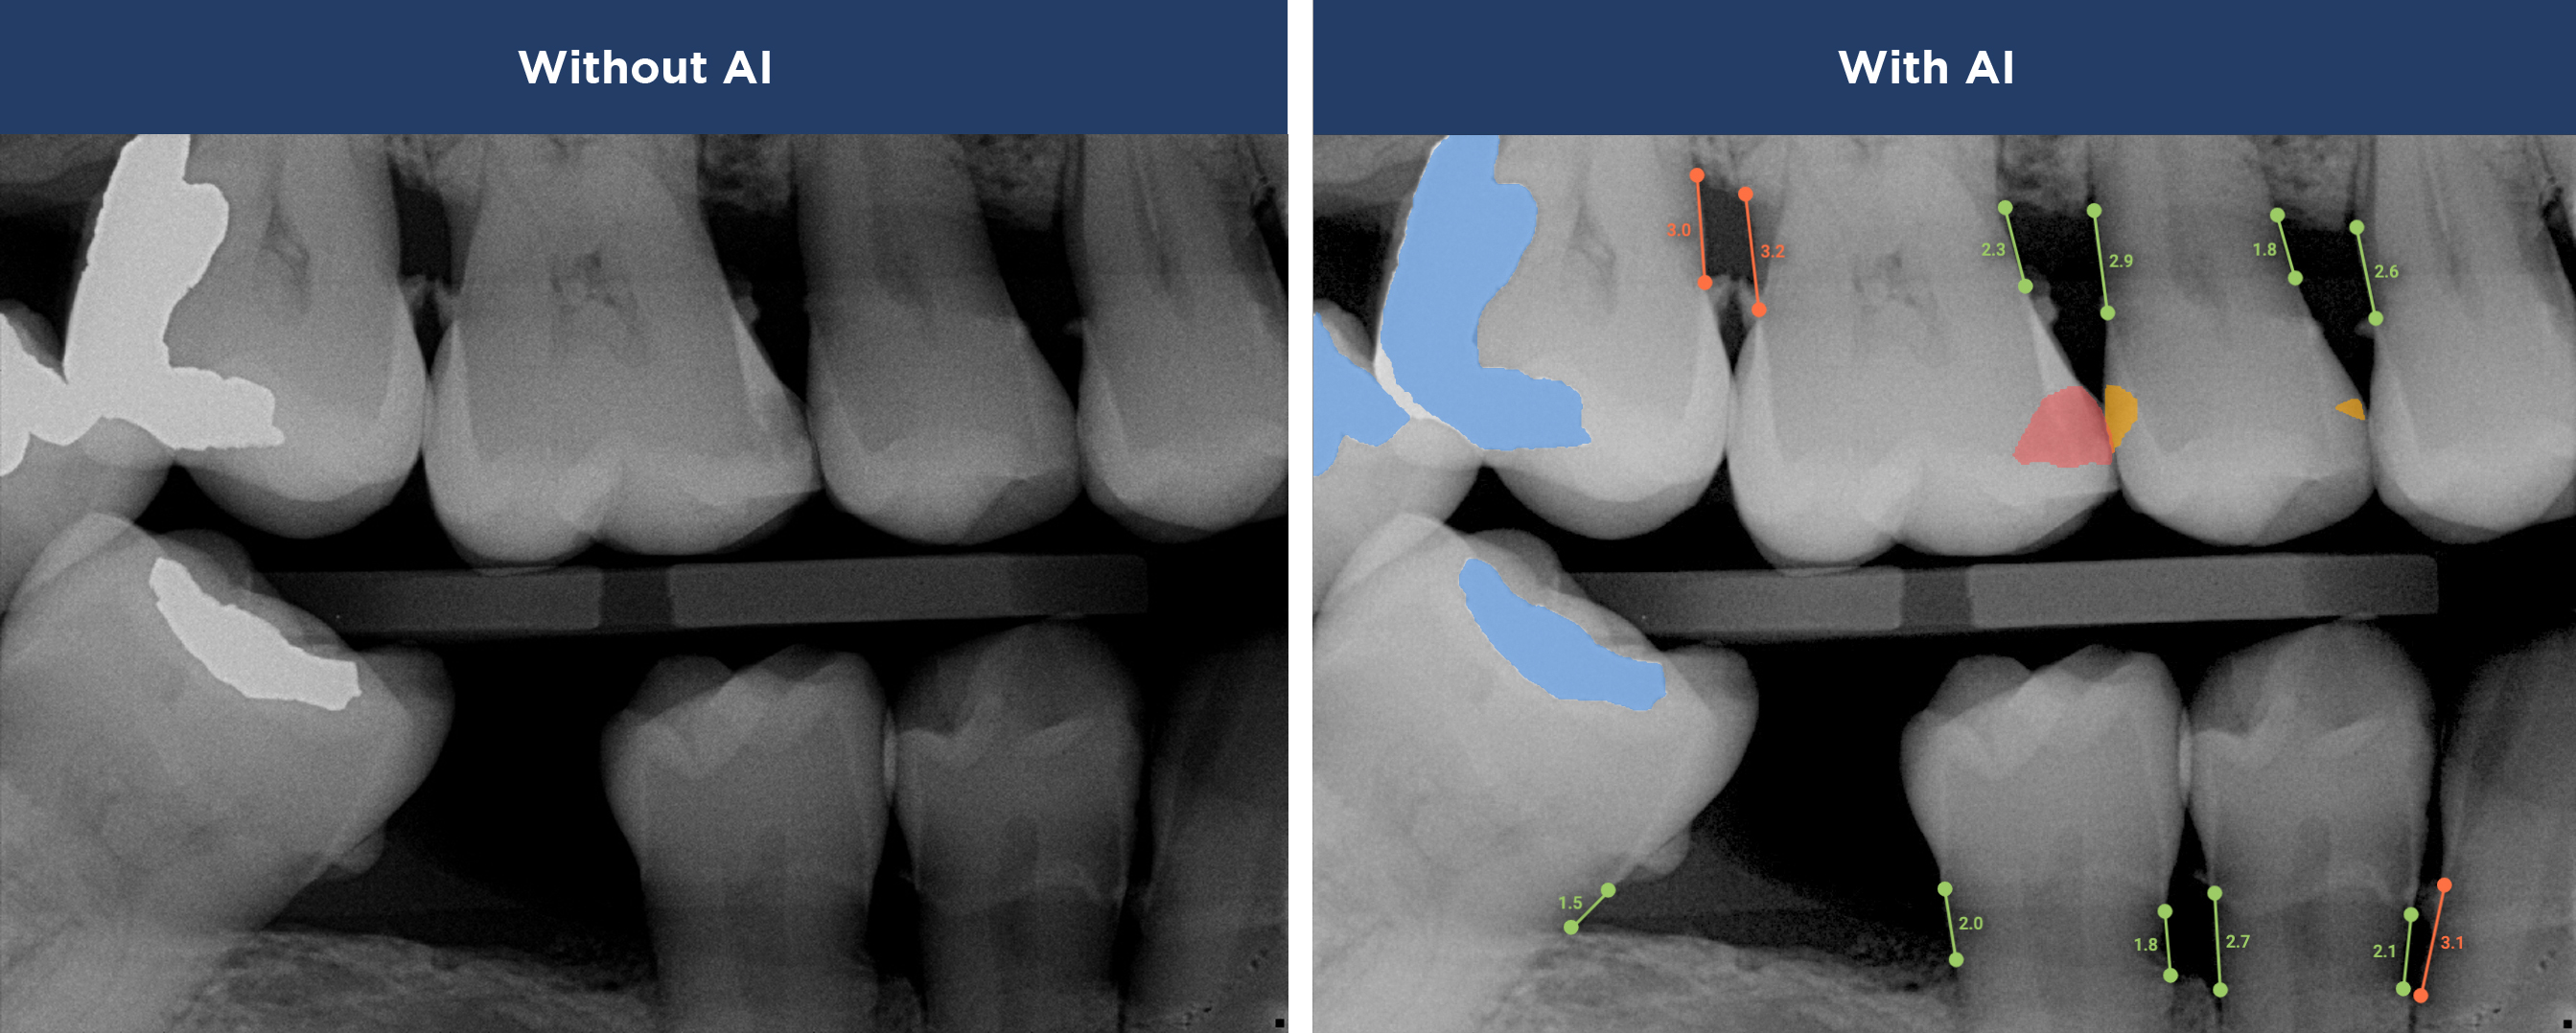

Our practice is proud to provide the best technology in the dental industry, including Overjet AI for instant X-ray analysis.

Overjet’s artificial intelligence technology transforms traditional black-and-white X-rays by adding a layer of data that instantly outlines decay (cavities) and measures bone loss. This makes it easy for you to see your results alongside your dentist.  It’s like getting a second opinion delivered instantly. With Overjet’s analysis and easy-to-read presentation, you will have the information you need to make an informed decision about your oral health. Together, we’ll review your findings and discuss the best steps to take to achieve your goals.